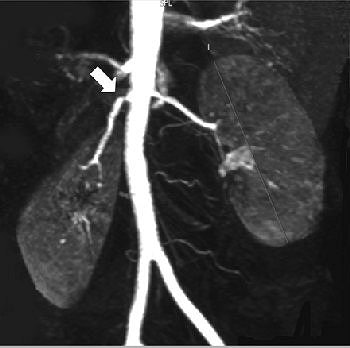

| Fifty-six-year-old healthy female living renal donor with stenosis of ostium of right renal artery. Above, volume maximum-intensity-projection MR angiography image using subtraction technique shows stenosis of ostium of right renal artery (arrow). Below, axial maximum-intensity-projection MR angiography image shows anterior origin of right renal artery with ostium stenosis (arrow). |